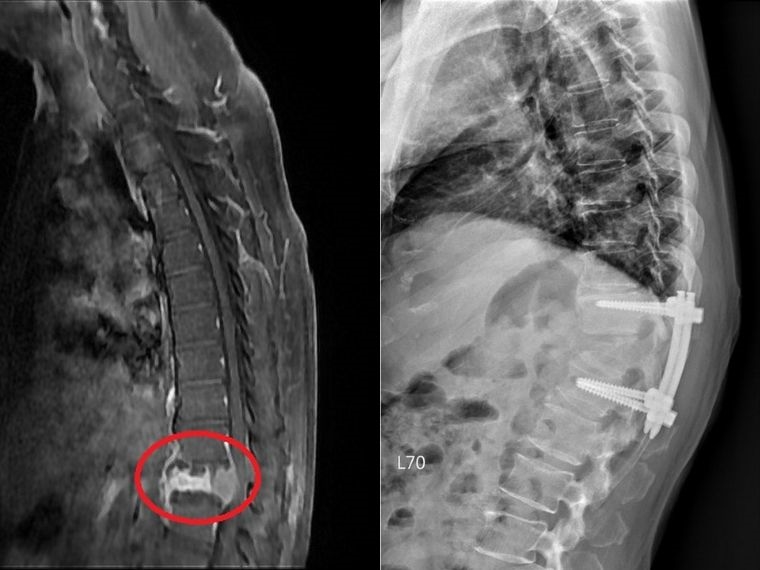

▲邱先生胸椎第12節有塌陷情形,且已經壓迫神經管,影像懷疑為腫瘤骨轉移導致的非單純骨質疏鬆之壓迫性骨折。(圖/台北慈濟醫院提供)

【NOW健康 翁靖祐/新北報導】60歲的邱先生過往沒有慢性病史也沒有特別定期健檢,1個月前突然出現雙腳無力的狀況,並且越來越嚴重,來院前無法站立行走,輾轉來到台北慈濟醫院神經外科洪立偉醫師門診尋求協助。透過X光、核磁共振檢查,發現邱先生胸椎第12節有塌陷情形,且已經壓迫神經管,影像懷疑為腫瘤骨轉移導致的非單純骨質疏鬆之壓迫性骨折,進一步抽血檢查更顯示腫瘤標記數值增高。經解釋後,洪立偉醫師遂執行「減壓及微創釘手術」,解除壓迫危機,術後隔天邱先生已能下床行走,並在傷口穩定後由腫瘤科團隊接手治療。

神經管受壓迫須進行良好的減壓,才可以讓神經學症狀達到改善,以邱先生為例,醫師在術中除給予良好的減壓外,還進行微創釘固定,幫助穩定脊椎。「減壓及微創釘手術」首先需要將脊椎後側的椎板切除進行完整減壓後移除部分腫瘤,並透過術中X光檢查確認位置,將4根微創骨釘分別固定在胸椎第11節及腰椎第1節,最後再以金屬桿連接兩端,不需破壞很多肌肉層即可達到穩定脊椎的作用。而過去手術通常使用的是傳統骨釘,術中需要劃一20公分的傷口,分離背部肌肉後將8根傳統釘固定於病灶上下各兩節脊椎處。